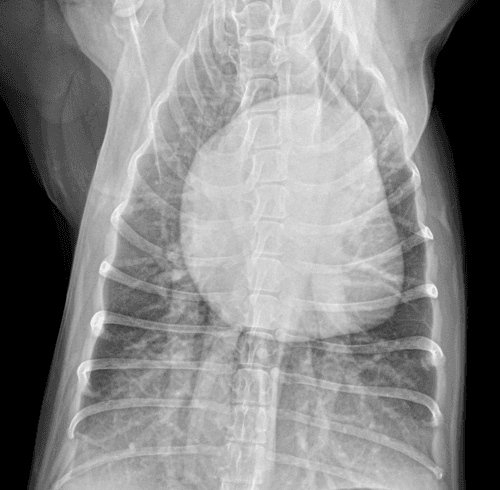

cardiologia veterinaria a vicenza

Medicina cardiovascolare è pratica specialistica della medicina interna che coinvolge il cuore, i vasi sanguigni e spesso il sistema respiratorio.

Malattie cardiache sono comuni negli animali da compagnia, e spesso possono essere trattate con successo o addirittura guarite.

Cardiologi veterinari usano la loro preparazione specialistica, una serie di test diagnostici e apparecchiature di immagine per arrivare alla diagnosi.

Indagine del apparato cardiocircolatorio inizia con un esame fisico con particolare attenzione sui fattori che indicano la funzione cardiaca, come il colore delle mucose orali, tempo di riempimento capillare, frequenza cardiaca a riposo, ritmo cardiaco, auscultazione cardiaca e polmonare, la frequenza respiratoria a riposo.

La malattia di cuore può essere primaria o secondaria ad altre condizioni come l'ipertensione, malattie della tiroide, disturbi elettrolitici, malattie infettive, malattie respiratorie e cancro. Cronica insufficienza mitralica valvolare, cardiomiopatia (DCM, HCM), ipertensione polmonare, dotto arterioso pervio (PDA), stenosi subaortica (SAS), stenosi polmonare (PS), difetto del setto ventricolare (VSD), insufficienza cardiaca congestizia (CHF), tachicardie, bradicardie e versamento pericardico sono alcune delle condizioni che comunemente riscontriamo nel cane e nel gatto.

Malattia cardiaca (l’insufficienza cardiaca) può avere l’origine congenita (5% dei casi presentati alla visita clinica) restanti 95% dei casi della malattia cardiaca è di origine acquisita. Proprio questa malattia cardiaca acquisita è uno dei problemi più comuni nei cani di mezza età e nei cani anziani.

Nella nostra clinica controllo cardiologico avviene alla prima visita clinica del cucciolo, in età di 55 – 60 gg per escludere eventuali cause congenite della malattia cardiaca. Dopo l’età di 7 anni nei cani e nei gatti è consigliata la visita cardiologica che consiste in esame fisico, controllo dell’attività elettrica del cuore (elettrocardiogramma – ECG), esame radiografico e esame tomografico-ecocardiografico (esame più valido nello studio delle valvole cardiache).